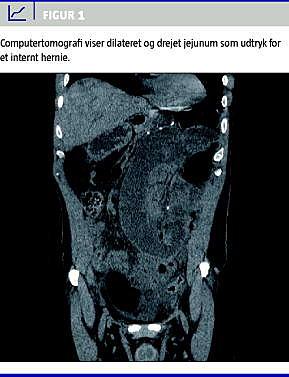

I. En 56-årig mand, der havde fået foretaget laparoskopisk gastrisk bypass to år tidligere, blev indlagt efter et døgn med tiltagende kraftige venstresidige mavesmerter, opkastninger, afføringsstop og en temperatur på 37,9 °C. Ved objektiv undersøgelse fandtes abdomen at være spændt overalt med anstrengte tarmlyde. Der blev udført akut computertomografi med kontrast, der viste ukomplet tyndtarmsileus med dilatation af proksimale jejunum på 5 cm (Figur 1 ). Klinisk overvejede man herniering, men havde ikke mistanke om tarmiskæmi. Tre timer senere fik patienten det alment dårligere med blodtingerede opkastninger, og ved fornyet klinisk undersøgelse var han peritoneal. Han blev herefter overflyttet til en specialafdeling, hvor man ved akut operation fandt ca. en meter iskæmisk tyndtarm, der var hernieret ind under jejuno-jejunostomien. Der blev foretaget tyndtarmsresektion med lukning af defekterne i abdomen, og herefter havde patienten et ukompliceret efterforløb.